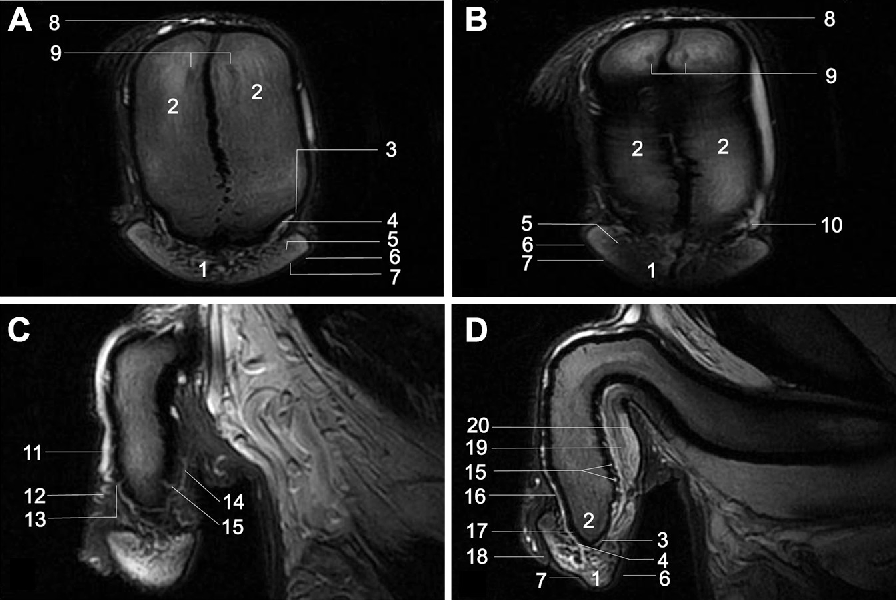

Hypospadias

1. Urinary opening on undersurface of the penis.

2. Surgical correction preferably completed before 2 yrs age and may be started at 1 or 1½ yrs.